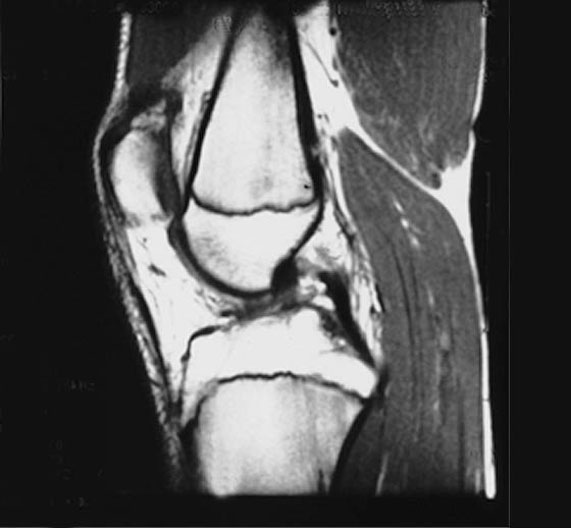

Knee MRI - Sagittal View

1. Femur

2. Epiphyseal plate of femur

3. Patellar ligament

4. Epiphyseal plate of tibia

5. Tibia

6. Hamstrings

7. Fat

8. Posterior cruciate ligament

9. Gastrocnemius